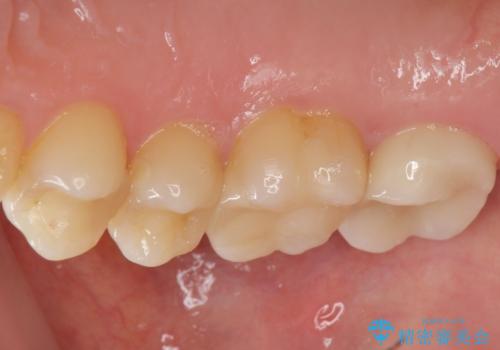

天然歯と変わらない色調に優れるセラミック治療の仕上がりに満足いただくことができました。

- 20.9万円(ジルコニアクラウン・仮歯・セラミックインレー)費用は治療当時の料金となります